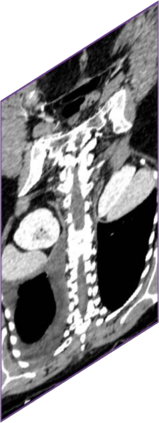

Due to the constraints of the imaging device and high cost in operation time, computer tomography (CT) scans are usually acquired with low intra-slice resolution. Improving the intra-slice resolution is beneficial to the disease diagnosis for both human experts and computer-aided systems. To this end, this paper builds a novel medical slice synthesis to increase the between-slice resolution. Considering that the ground-truth intermediate medical slices are always absent in clinical practice, we introduce the incremental cross-view mutual distillation strategy to accomplish this task in the self-supervised learning manner. Specifically, we model this problem from three different views: slice-wise interpolation from axial view and pixel-wise interpolation from coronal and sagittal views. Under this circumstance, the models learned from different views can distill valuable knowledge to guide the learning processes of each other. We can repeat this process to make the models synthesize intermediate slice data with increasing inter-slice resolution. To demonstrate the effectiveness of the proposed approach, we conduct comprehensive experiments on a large-scale CT dataset. Quantitative and qualitative comparison results show that our method outperforms state-of-the-art algorithms by clear margins.